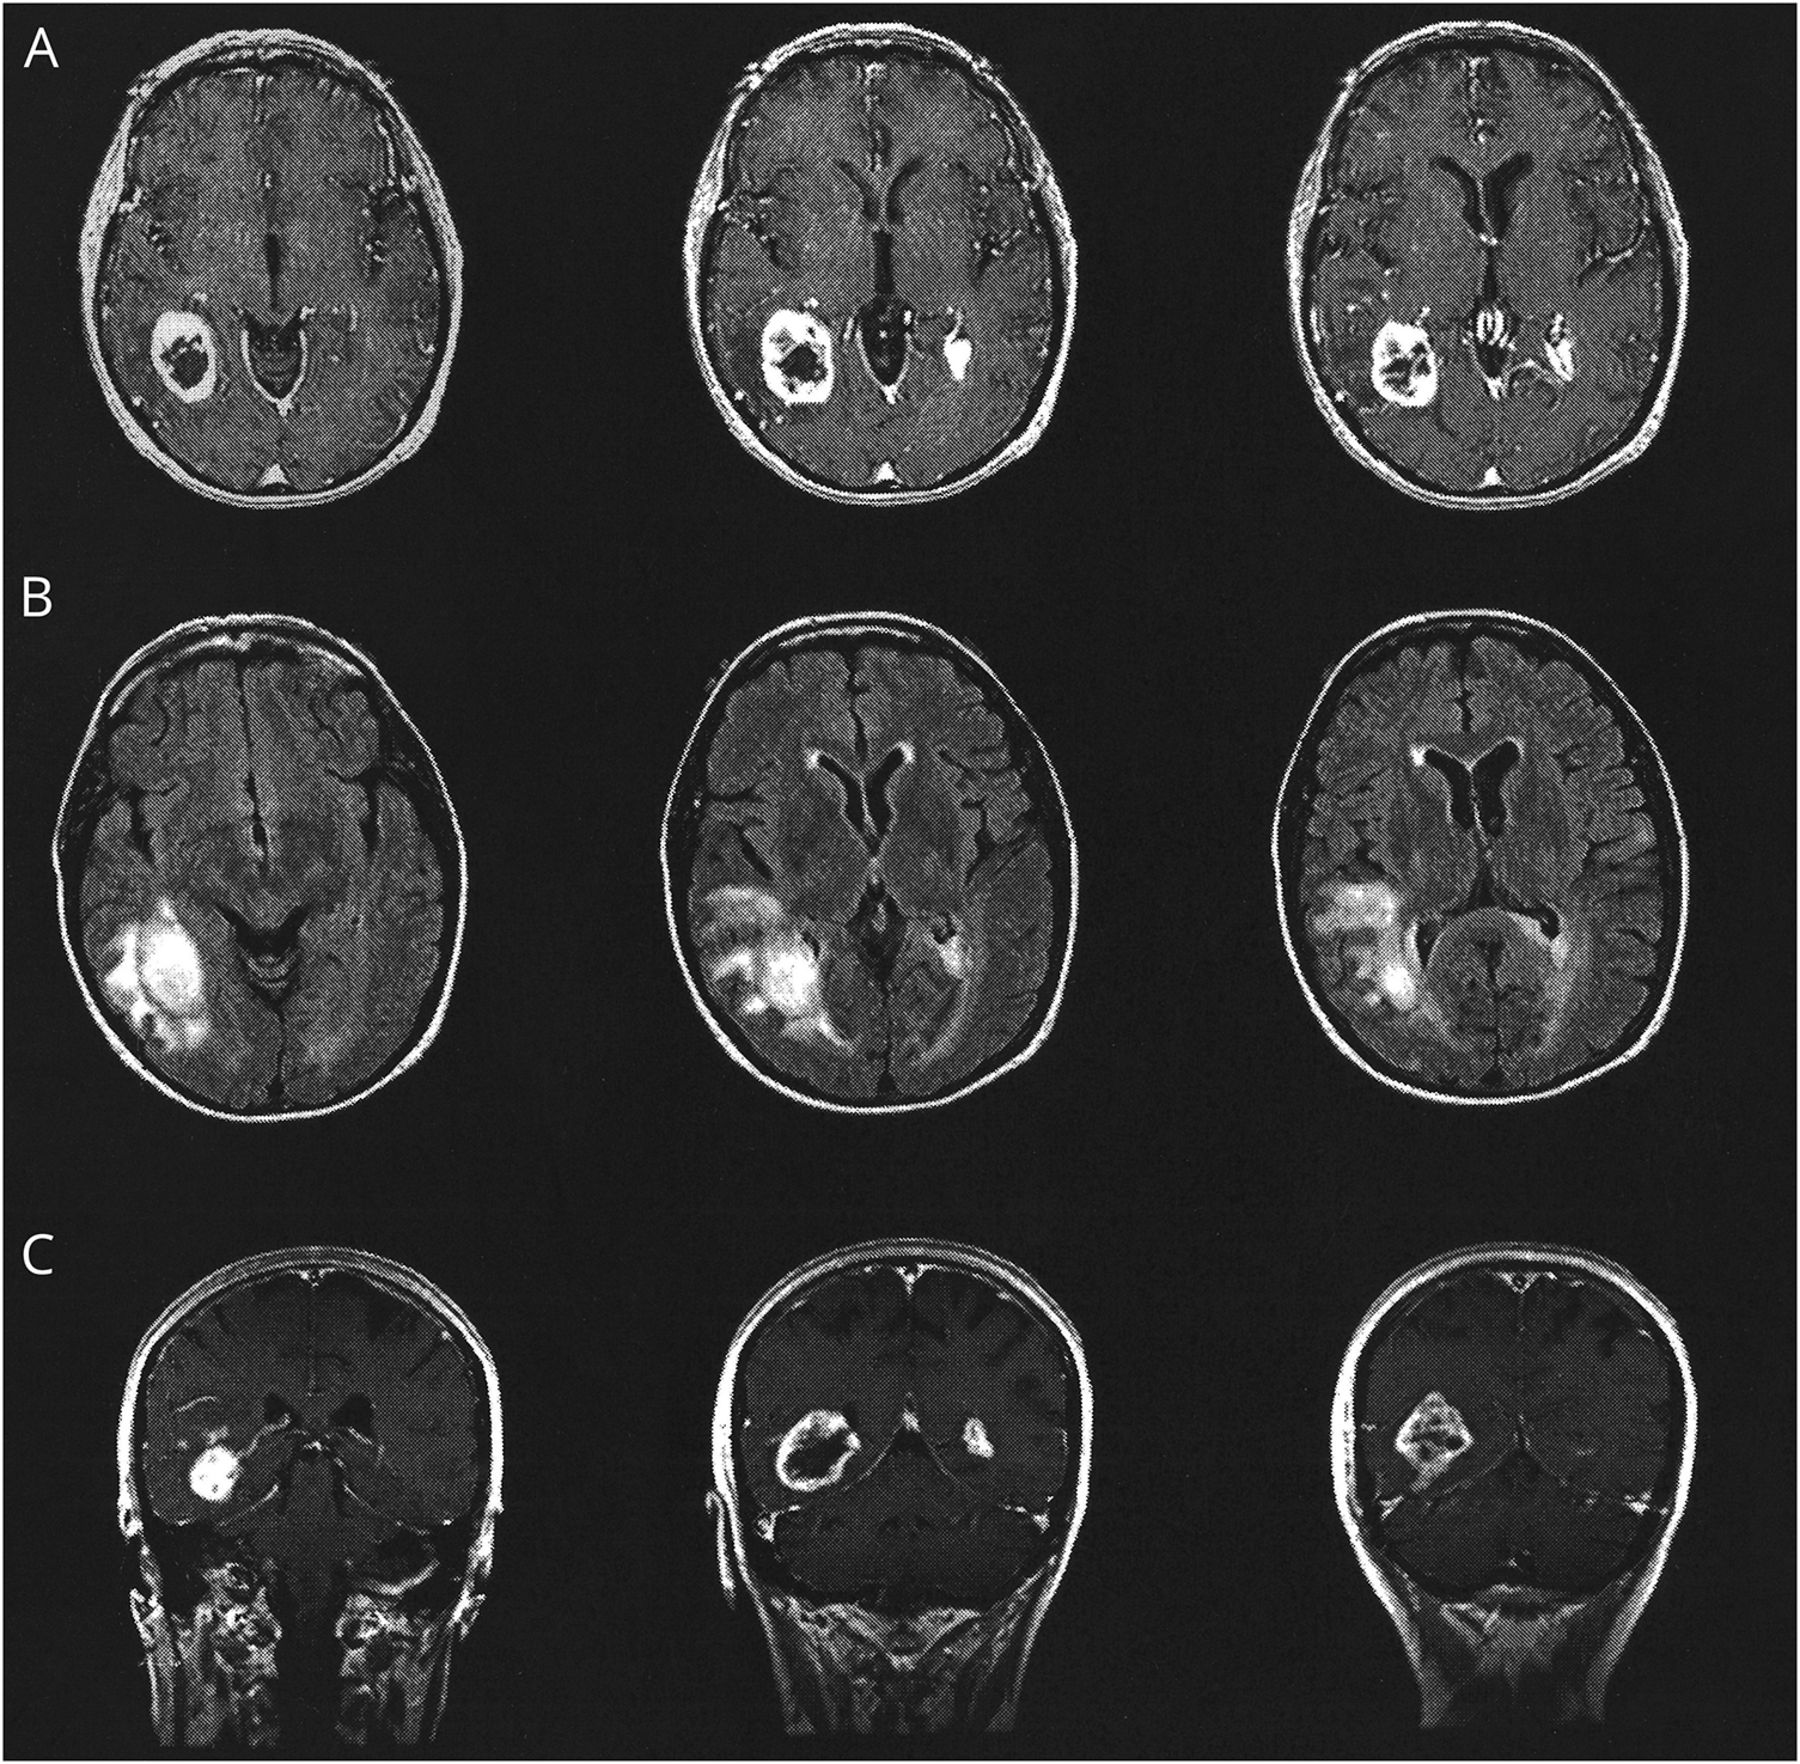

病人被称为大脑的核磁共振扫描来评估颅内异常。MRI显示变化符合多焦bihemispheric高档神经胶质瘤(图)。有一个大的提高区域周围水肿的temporo-occipital叶。这是最著名的网站。第二个增强病灶位于左顶叶白质与扩展在胼胝体压部。也有不正常的信号出现在T2 fluid-attenuated反转恢复图像涉及左额叶脑回。基于这些发现,病人被称为活组织检查。在高等院校,她提到了活组织检查,她的神经系统检查是重要的只剩下了视觉注意力不集中,同时两国刺激,建议左hemispatial忽视,除了面容失认症。活组织检查的权利temporo-occipital肿瘤显示多形性成胶质细胞瘤。放疗和化疗的病人被称为。

轴向超声造影被宠坏的梯度回忆图片(A),轴向fluid-attenuated恢复图像(B)和日冕对比度增强t1加权自旋回波图像(C)展示多个充当群众涉及右temporo-occipital叶和左顶叶心房区域。占主导地位的大众正确的temporo-occipital叶与温和的周围的水肿和质量效应。这种病变活检和显示多形性成胶质细胞瘤。